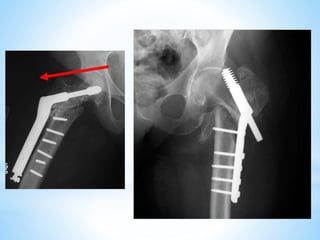

This document discusses the treatment of intertrochanteric hip fractures with different fixation devices. It notes that cephalomedullary devices are preferable to dynamic hip screws for fractures with posteromedial comminution or subtrochanteric extension due to their ability to provide controlled collapse and reduce bending forces. The document emphasizes the importance of pre-operative planning, proper reduction techniques, and achieving a tip-apex distance under 25mm for successful fixation with cephalomedullary devices.